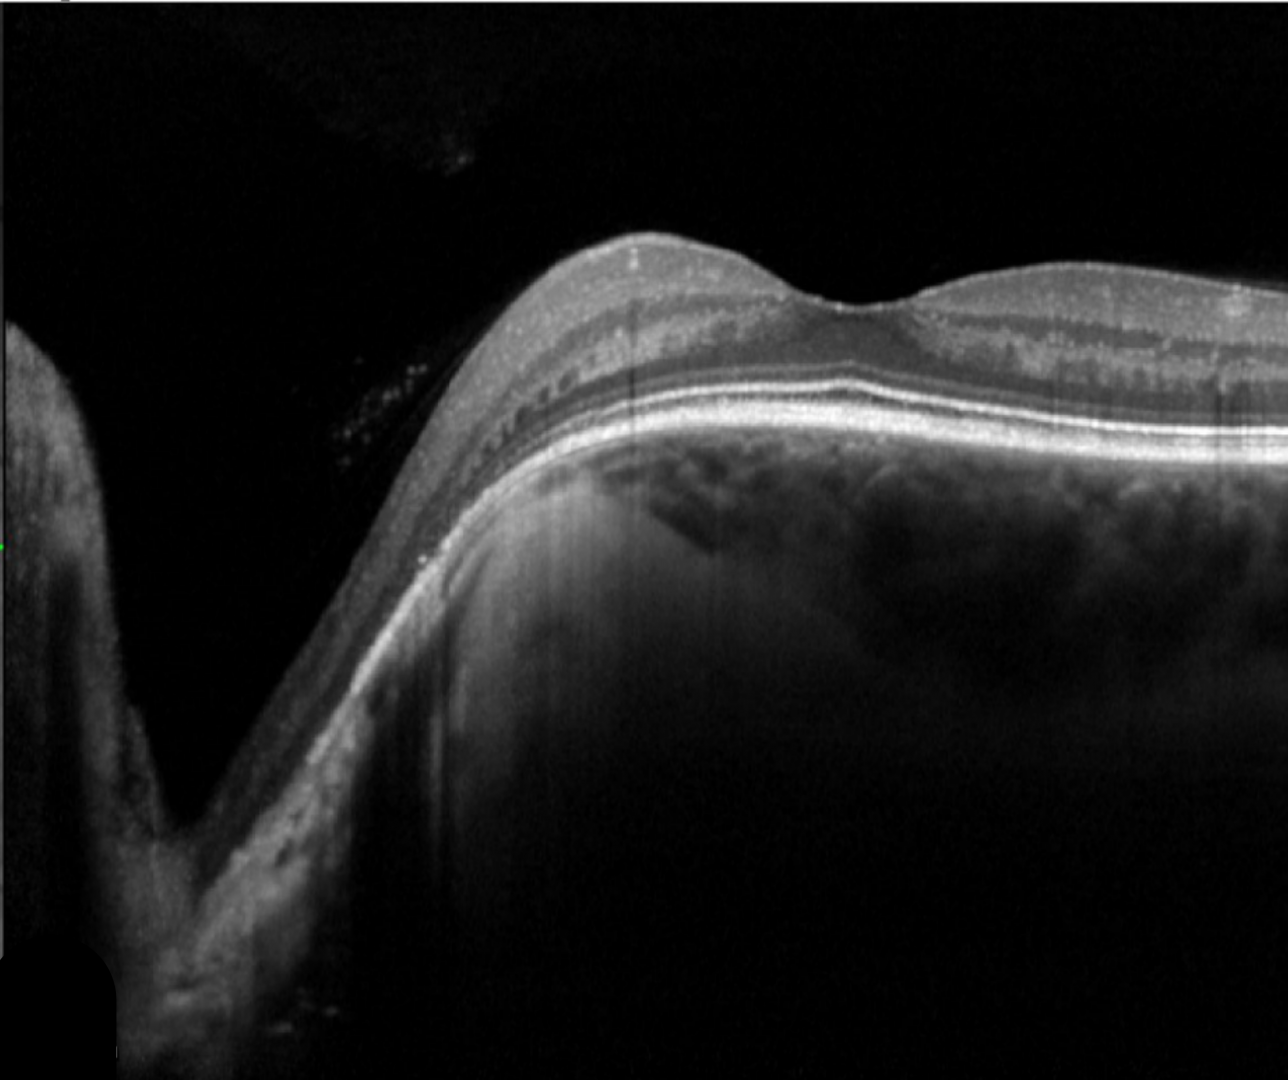

Case 3: Optic disc pit maculopathy

A 57 year old asymptomatic Asian female with best corrected visual acuity of 6/6 (20/20) in each eye.